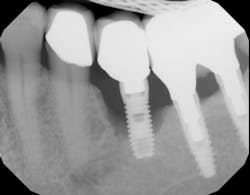

The effect PPIs have on implants is not clear, but one study looked at 3,560 implants placed in 1,000 patients over a 35-year period. Results found a 12% failure rate in PPI users versus nonusers.8 Another study evaluated 1,773 implants placed in 800 patients and found the failure rate doubled when comparing PPI users and nonusers.9 When unexplained bone loss occurs around an implant and the patient has been on long-standing PPI medication, consideration should be given to this possible etiology (figure 2).